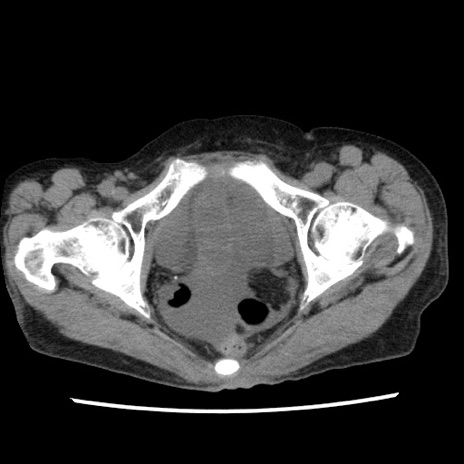

症例1(横断像)

【症例】80歳代女性

【主訴】腹痛

【現病歴】8時間前から腹痛あり来院。

【既往歴】糖尿病、脂質異常症、子宮体癌にて子宮全摘術

【身体所見】意識清明・会話良好だが腹痛で苦悶様、全腹部にわたって反跳痛と圧痛あり

【データ】WBC 13600、CRP 0.14、LDH 224、CK 90